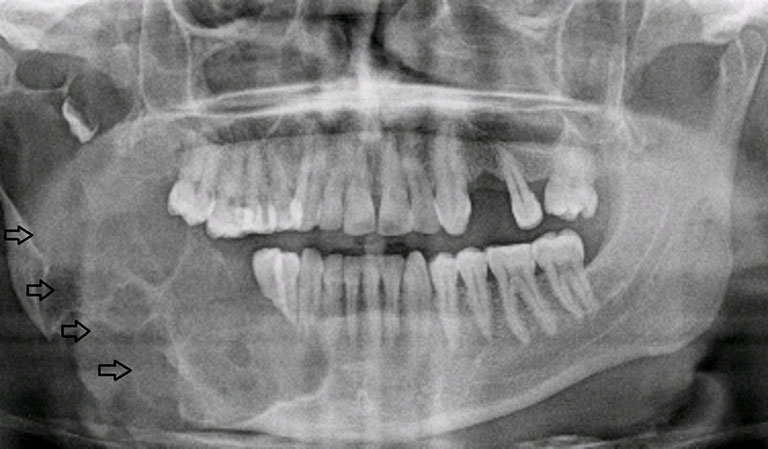

Để chẩn đoán u men răng, bác sĩ sẽ tiến hành kết hợp nhiều phương pháp khác nhau. Chụp X-quang và CT Cone Beam thường được sử dụng để quan sát khối u, đánh giá mức độ xâm lấn và phá hủy xương. Ngoài ra, sinh thiết mô cũng là bước quan trọng nhằm xác định bản chất lành tính của khối u.

Ở giai đoạn đầu, hình ảnh X-quang có thể cho thấy một hoặc nhiều vùng sáng tối bất thường trong xương hàm, gọi là hình ảnh “tổ ong” hoặc “bọt xà phòng”. Đây là dấu hiệu đặc trưng giúp phân biệt u men răng với các bệnh lý khác trong xương hàm.